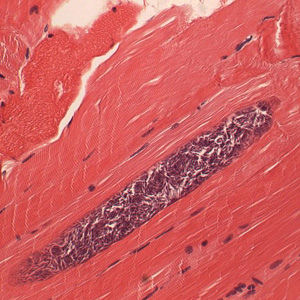

Острая форма, встречающаяся относительно редко, характеризуется лихорадкой, анемией, мышечной слабостью и отеками. Хроническое течение сопровождается прогрессирующим истощением, мышечной атрофией и нарушением координации движений. При патологоанатомическом исследовании обнаруживаются характерные беловатые цисты в мышечной ткани размером 1-10 миллиметров, гидремия мышечной ткани, а в хронических случаях - кальцификация цист и общее истощение организма.

Прижизненная диагностика саркоцистоза может осуществляться серологическими реакциями с сывороткой крови. Диагностику саркоцистоза у плотоядных проводят путем исследования фекалий. Также используют лабораторные методы исследования: микроскопию мышечных волокон, серологические реакции (РСК, РДСК, ИФА, ПЦР и другие).

При дифференциальной диагностике цисты саркоцист крупного рогатого скота, овец и свиней следует отличать от капсул с трихинеллами, цистицерков (особенно молодых), безноитий, токсоплазм, изоспор, хаммондий, гонгилонем, личинок подкожного овода, а также кальцификатов.

При посмертной диагностике исследуют компрессорными методами мышцы диафрагмы, языка, межрёберные и жевательные.